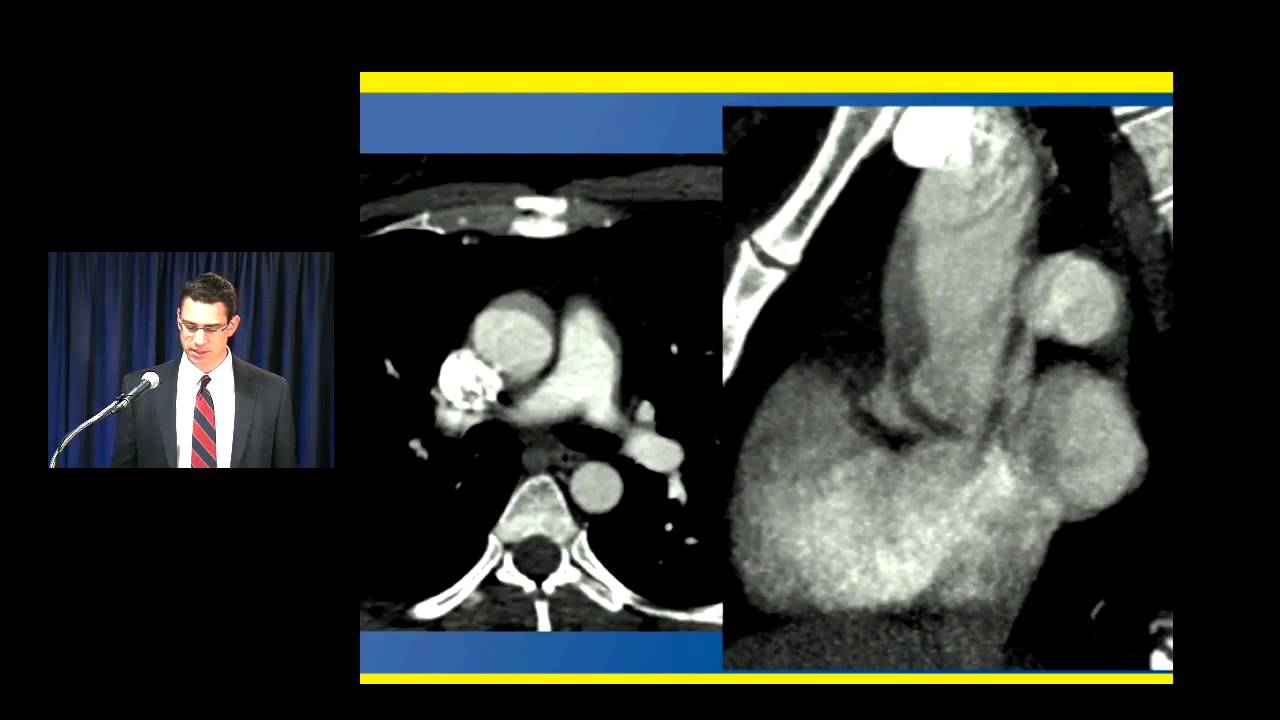

so let's look at this unguided study on a young woman who came in with chest pain and has what looks like a small dissection in the a semi thoracic aorta now we have all seen the pulsation artifact that looks like a dissection and in this case very well could be a pulsation artifact but she had a very strong clinical suspicion for dissection and we couldn't be absolutely sure that this wasn't a dissection so she was imaged the following day with a gated study look at the difference the case on the right there is no artifact

there is no dissection and there is no question so patient with chest pain and a concern for a sending thoracic dissection you have to perform a gated acquisition same patient every set of presentations axial sagittal coronal looked like there was a dissection on the first undated study and is clearly normal on the gated acquisition coronary artery imaging we need a gated acquisition so that we can evaluate these small vessels we're at a point in the cardiac cycle where the motion artifact is minimized here is a patient who had was being imaged actually for the ascending